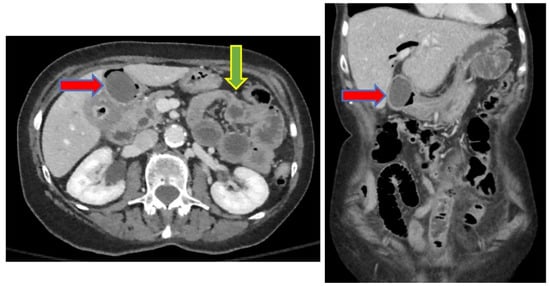

We report the case of an 83-year-old woman who presented to our emergency department (ED) with progressive worsening abdominal pain, nausea, and non-bloody, bilious emesis of one day’s duration that continued overnight in the ED. Her medical history includes coronary artery disease status following angioplasty and stenting, in addition to choledocholithiasis with acute cholangitis requiring endoscopic retrograde cholangiopancreatography (ERCP) with sphincterotomy and percutaneous transhepatic biliary drainage (PTCD) approximately one year prior in her home country, Scotland. Regrettably, the patient’s PTCD tube became dislodged, and she began to develop severe abdominal pain, prompting presentation to our facility. There was no recent history of fever, jaundice, acholic stools, or dark urine. A two-view abdominal radiograph was initially obtained showing a branching density over the liver relating to portal venous gas (Figure 1). Computerized tomography (CT) of her abdomen showed circumferential mid-jejunum bowel wall thickening with a mildly dilated bowel proximally, prominent mesenteric edema, mild intra- and extrahepatic biliary ductal dilatation with pneumobilia, perigastric inflammation, a contracted gallbladder, and probable obstructing mass in the first portion of the duodenum (Figure 2). She developed peritoneal symptoms and was taken urgently for an exploratory laparotomy.

Figure 2. CT abdomen showing duodenal obstructing mass (red arrow) and mid-jejunum transition point (green arrow). The figure on the left is an axial slice and on the right is a coronal slice.